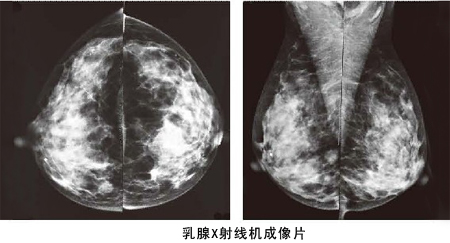

鉬靶X線

鉬靶X線則是目前乳腺疾病檢查、發(fā)現(xiàn)和診斷早期乳腺癌的有效手段。BTX-9800A型鉬靶X線機(jī)采用現(xiàn)代科學(xué)技術(shù),自動(dòng)化程度高,圖像清晰;人性化的設(shè)計(jì)使操作極為方便,成為乳腺疾病影像學(xué)診斷中的重要設(shè)備。